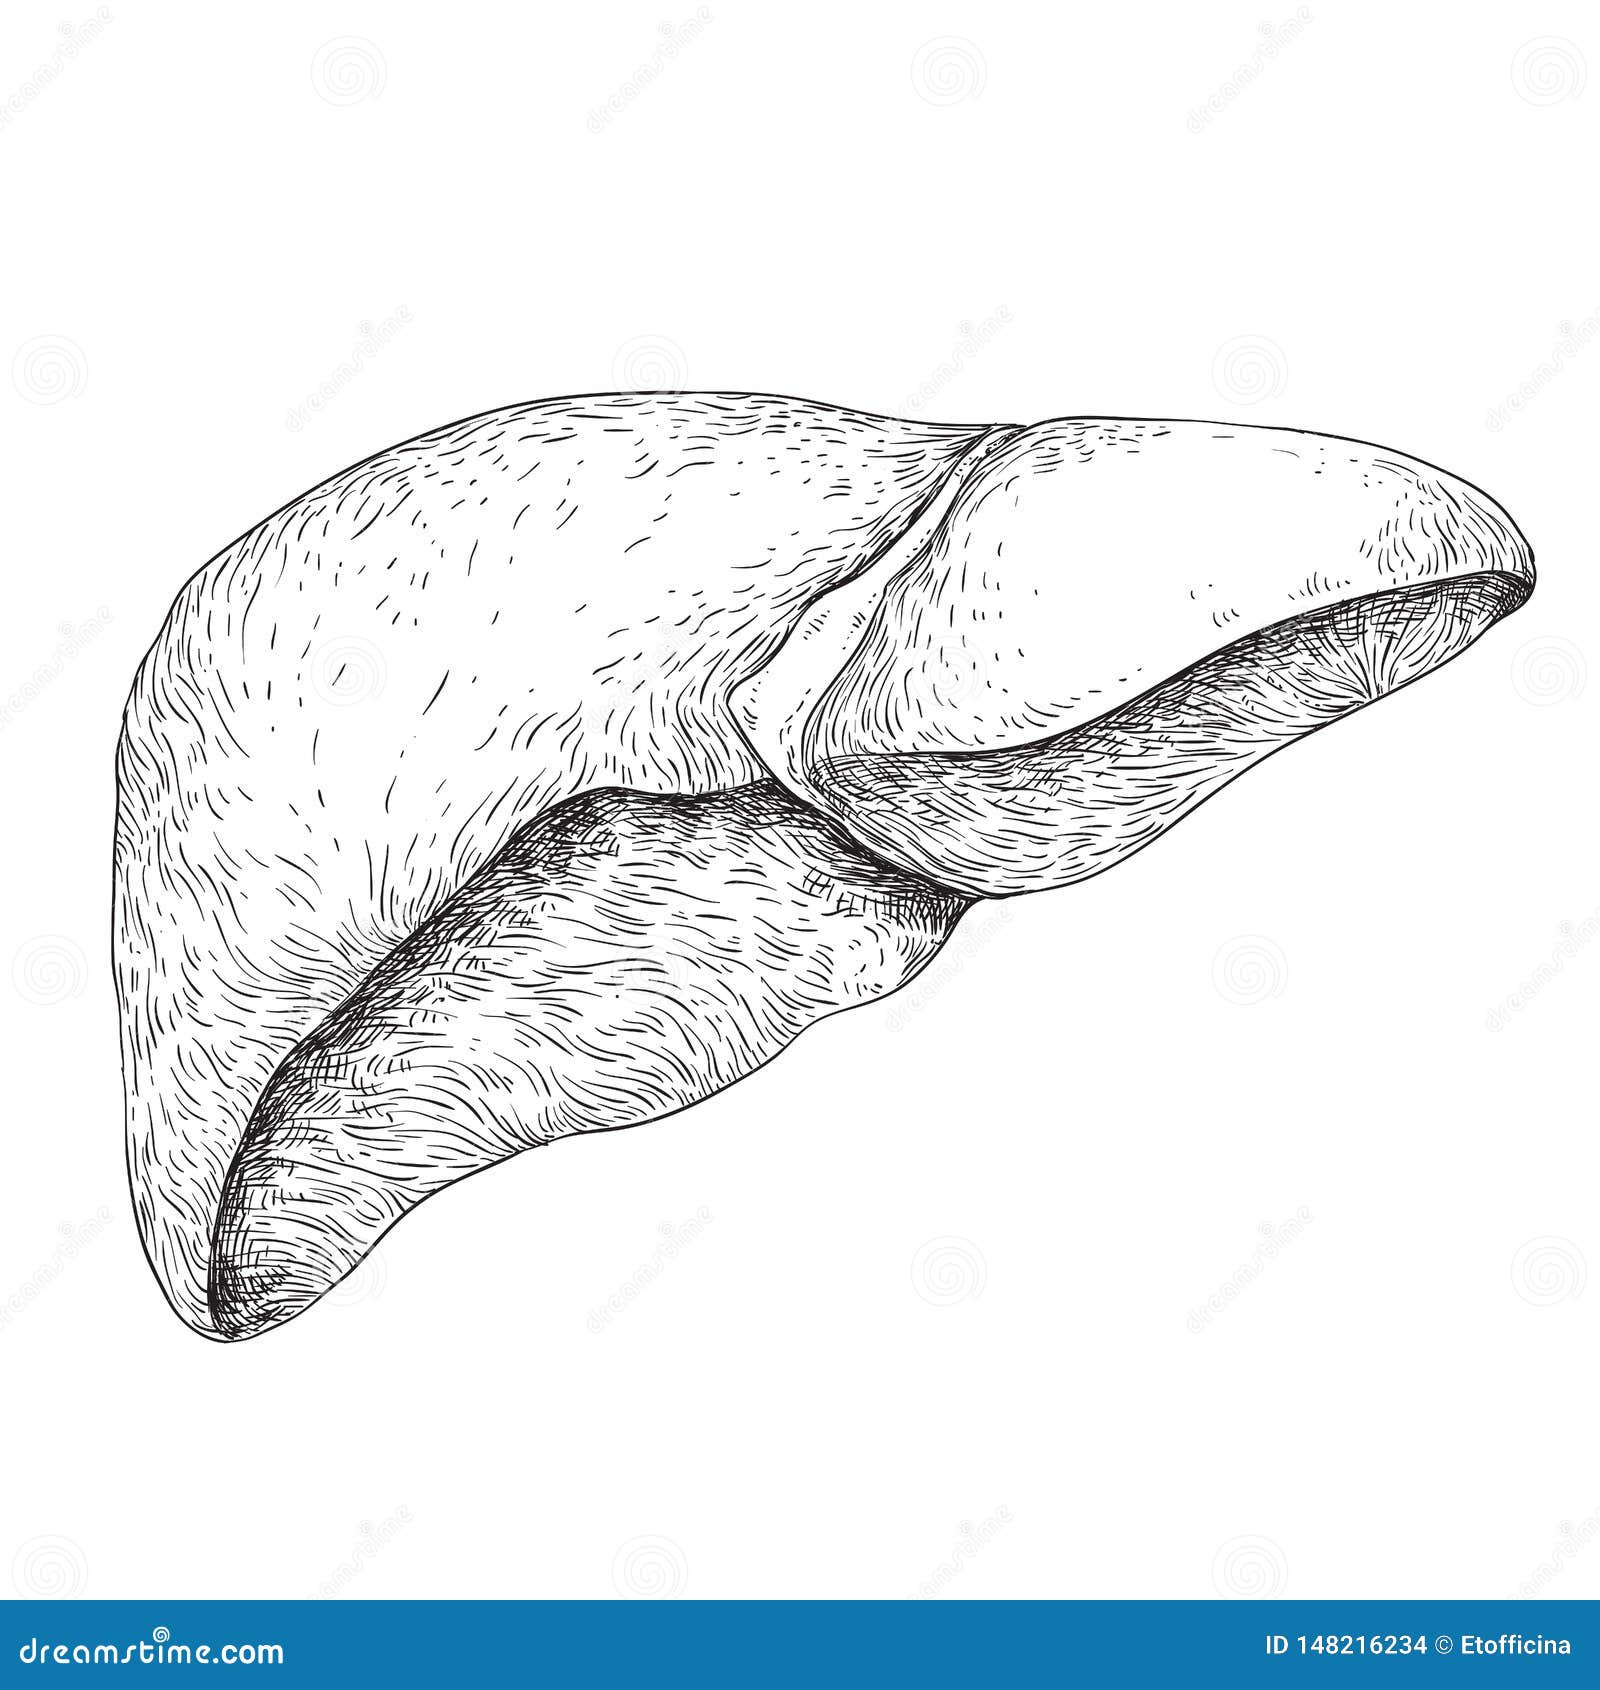

Печень, один из самых крупных и важных органов человеческого тела, выполняет множество жизненно необходимых функций, включая фильтрацию токсинов и производство жизненно важных белков. В данной статье мы рассмотрим, как наглядные изображения печени могут помочь лучше понять её структуру, функции и возможные заболевания. Использование рисунков и диаграмм делает сложные биологические процессы более доступными для понимания, особенно важно это для студентов, врачей и пациентов, стремящихся глубже изучить этот ключевой орган.

Печень рисунок